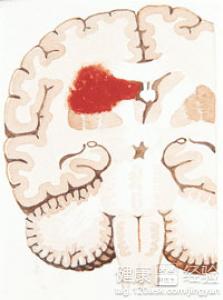

腦血管疾病怎麼治療